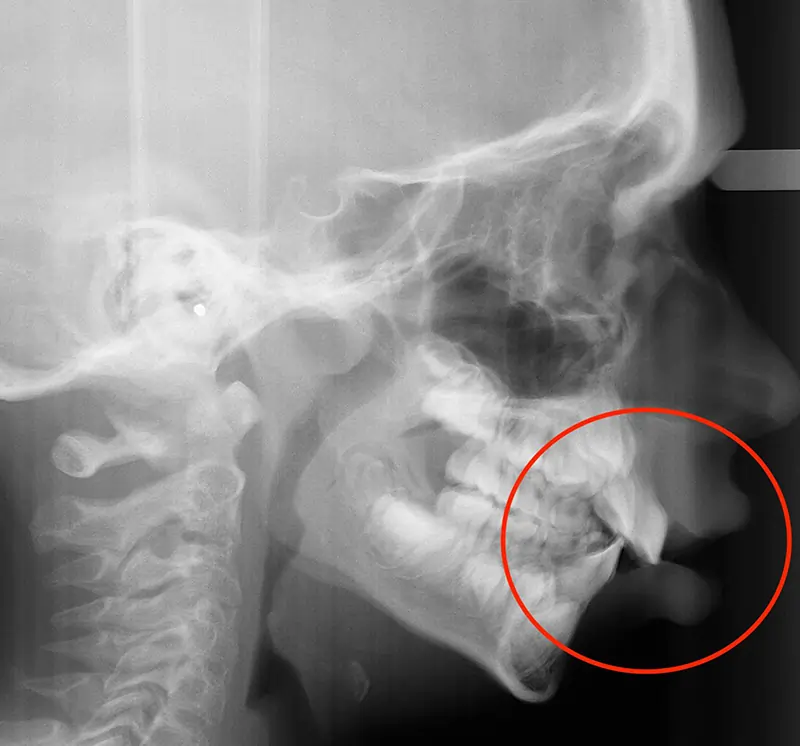

Actual Patient: Alexander

Alexander Before 4 Alexander After 4

Severe “Underbite”, Narrow Jaws, Adult Teeth Not Growing In

Alexander Before 1 Alexander After 1

Front View Results

0 Month

6 Month

11 Month

Side View Results